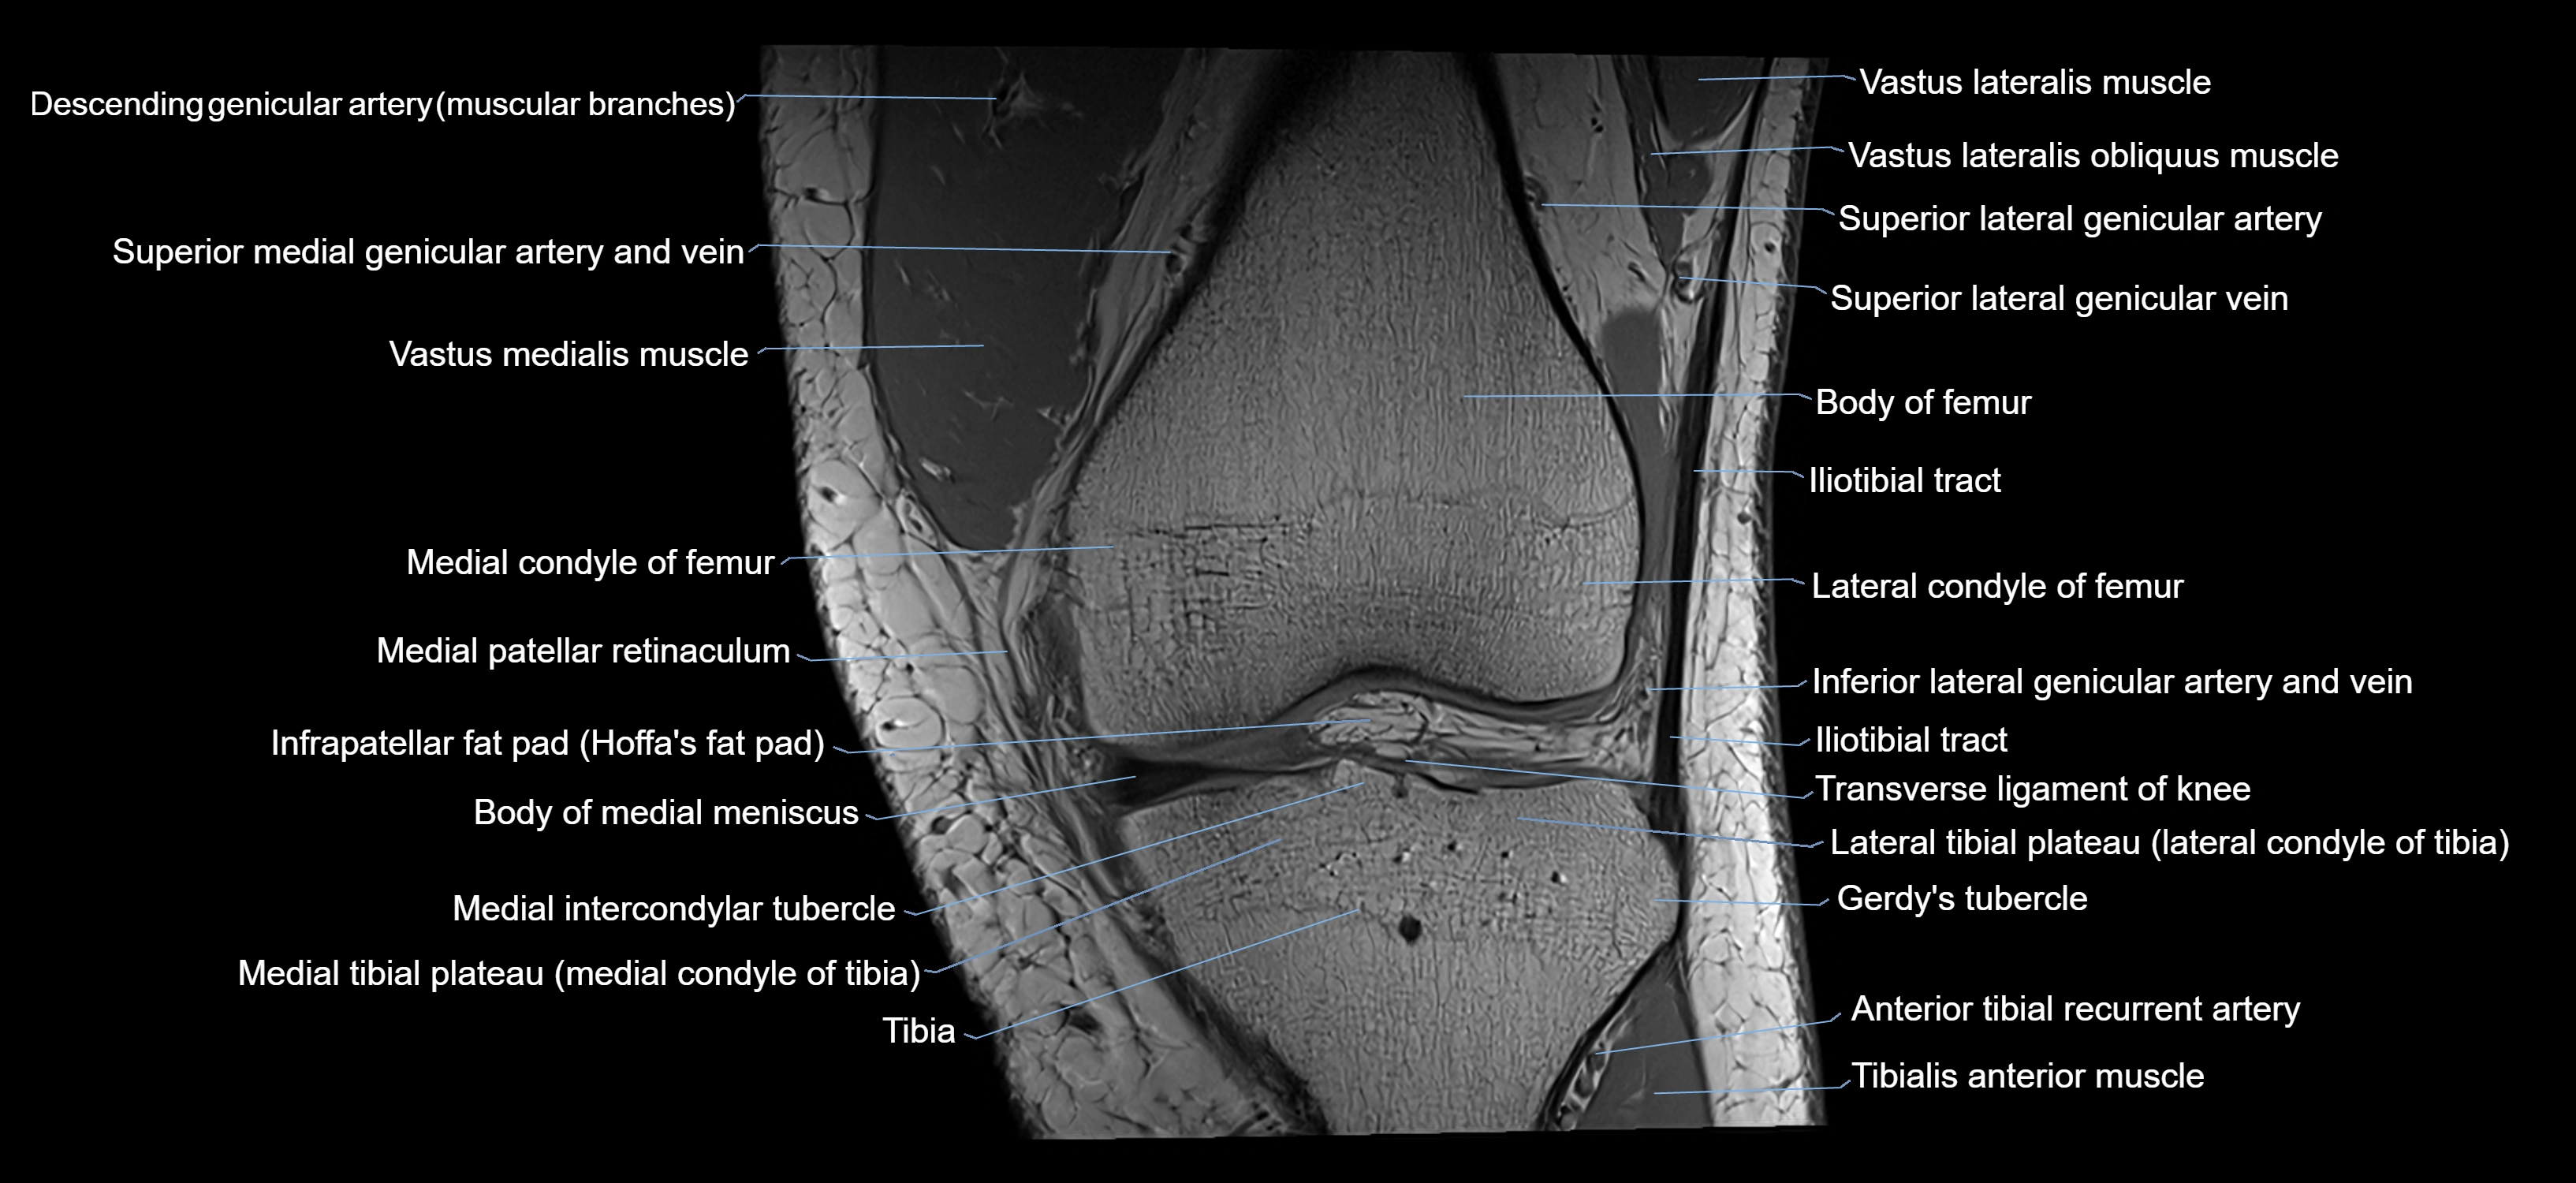

- Body of femur

- Body of medial meniscus

- Gerdy’s tubercle

- Infrapatellar fat pad

- Lateral condyle of femur

- Lateral condyle of tibia

- Lateral patellar retinaculum

- Lateral tibial plateau

- Medial condyle of femur

- Medial condyle of tibia

- Medial intercondylar tubercle

- Medial patellar retinaculum

- Medial tibial plateau

- Superior lateral genicular artery

- Superior lateral genicular vein

- Tibia

- Tibialis anterior muscle

- Transverse ligament of knee

- Trochlear groove

- Vastus Lateralis Obliquus Muscle

- Vastus lateralis muscle

- Vastus medialis muscle